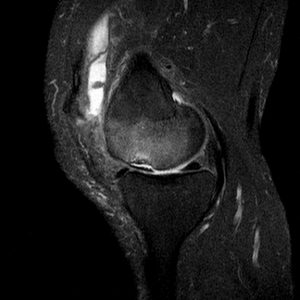

Die fettsupprimierte Magnetresonanztomographie (MRT) hat eine hohe Sensitivität und auch Spezifität, wobei nie genau der Inhalt eines Ergusses diagnostiziert werden kann (Abb.11 und 12).

Abb.11 hyperplastisch-zottige Synovialitis des Kniegelenkes im MRT